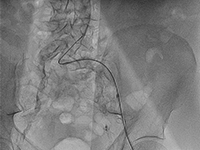

ChirurgiaSchyłkowa niewydolność nerek (SNN) jest narastającym problemem w krajach rozwiniętych [1]. Chociaż cukrzyca pozostaje najczęstszą przyczyną dysfunkcji tych narządów [2], przewlekła nefropatia może być spowodowana także chorobami autoimmunologicznymi, szczególnie z grupy zapaleń naczyń. W Stanach Zjednoczonych liczba pacjentów ze SNN wymagająca dializoterapii sięga już blisko 500 000, a ponad 200 000 żyje z czynnym przeszczepem nerki [3]. Przewlekła choroba nerek (PChN) stanowi znaczący problem kardiologiczny, przyczyniając się do szybkiego rozwoju choroby wieńcowej, a zwłaszcza postaci wielonaczyniowej. Na cięższy przebieg choroby wieńcowej u pacjentów z PChN wpływ mają zaburzony metabolizm wapnia i tendencja do rozsianego wapnienia tętnic [4]. Pacjenci z PChN i wysokim stężeniem CRP są obciążeni szczególnie dużym ryzykiem incydentów sercowo-naczyniowych [5,6]. Obecnie nie istnieją wytyczne dotyczące leczenia zabiegowego choroby wieńcowej u pacjentów z PChN. Występuje u nich jednak większe ryzyko zgonu po rewaskularyzacji niż w populacji bez PChN [7]. Zdania na temat skuteczności zastosowania u tych pacjentów przezskórnej interwencji wieńcowej (PCI) i pomostowania aortalno-wieńcowego (CABG) są podzielone i brak jednoznacznych danych w tym zakresie. Nie ma też zaleceń sugerujących opracowanie długoterminowej strategii leczenia choroby wieńcowej u pacjentów ze SNN, choć opisano, że wymagają oni wielokrotnych powtórzeń PCI (w przypadku wyboru tej metody) [8].